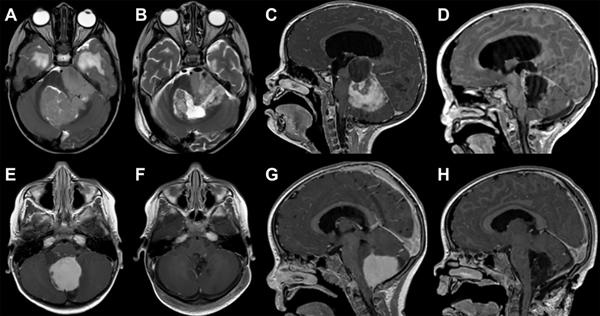

El grado de resección se categorizó como resección total (del inglés “gross total resection”, GTR), resección subtotal (“sub-total resection”, STR) y resección parcial (“partial resection”, PR), basado en la observación intraquirúrgica y de imágenes de RM postoperatorias (hasta 72 horas posteriores a la cirugía); GTR correspondió a la ausencia de restos tumorales en RM concordante con la apreciación intraquirúrgica de los neurocirujanos; STR correspondió a los casos en los que se observó un resto tumoral menor al 5% en RM o intraoperatorios como en los casos de invasión del tronco encefálico; PR, cualquier grado de resección que no cumplió los criterios anteriores (Figura 1).

Figura 1: Análisis comparativo de imágenes de resonancia magnética (RM) prequirúrgicas y postoperatorias, destacando los distintos grados de resección tumoral.

A y B: imagen axial de RM ponderada en T2 en el que se observa una lesión correspondiente a Ependimoma Anaplásico de fosa posterior y su resección parcial (PR) debido a la adherencia de la misma a la cara lateral del tronco encefálico.

C y D: imagen sagital de RM ponderada en T1 con gadolinio en la que se evidencia una lesión sólido-quística en fosa posterior, compatible con Astrocitoma pilocítico y la resección subtotal (STR) con un resto en región de la cisterna cuadrigeminal que se encontraba adherido.

E, F, G y H: Imágenes axiales y sagitales de RM ponderadas en T1 con gadolinio, de un paciente con lesión en fosa posterior compatible con Astrocitoma de fosa posterior y su resección completa (GTR).